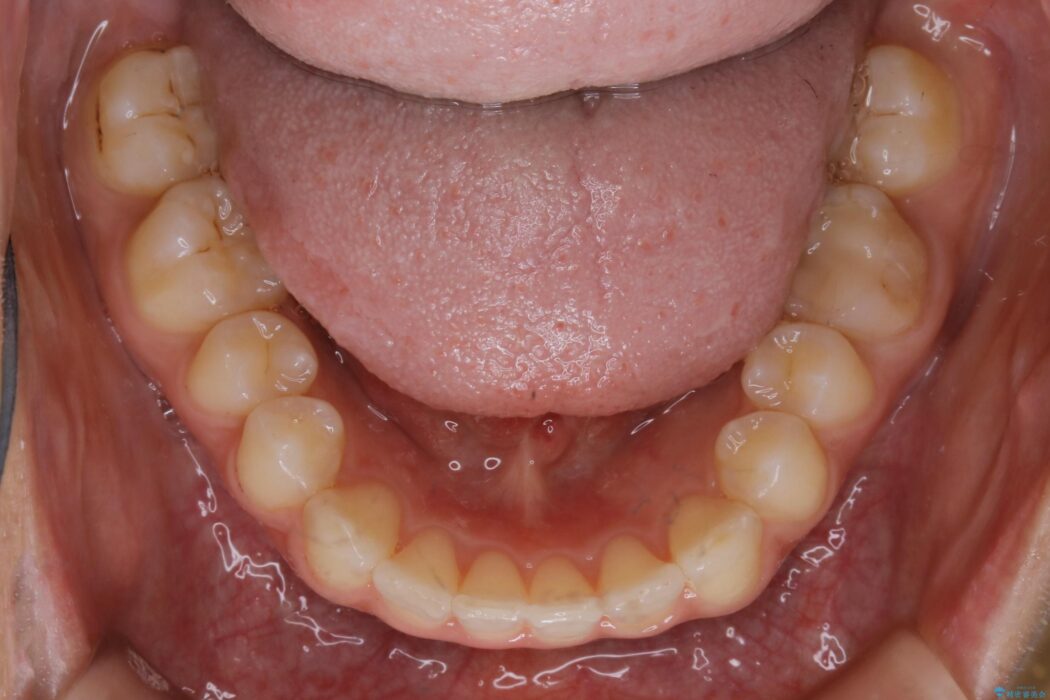

気になるガタツキと噛み合わせを改善したいとご来院されました。

下の歯列よりも上の歯列が前に出ている状態を治すため、マウスピース矯正に加え、患者様にゴムかけのご協力をいただきました。その結果、ガタつきが改善し、上下の噛み合わせが適切な位置で合うようになりました。

歯列弓の拡大

歯並びが悪くなる原因の一つに「歯列弓の狭窄」というものがあります。

奥歯や前歯が内側(舌側)に倒れ込んでしまったり、歯が生えてくる位置が内側になってしまうことにより歯並びのアーチが狭くなってしまうことを言います。

このような場合、歯並びのアーチを拡大してあげるだけでもガタつきを無くすためのスペースがかなり作れることがあります。